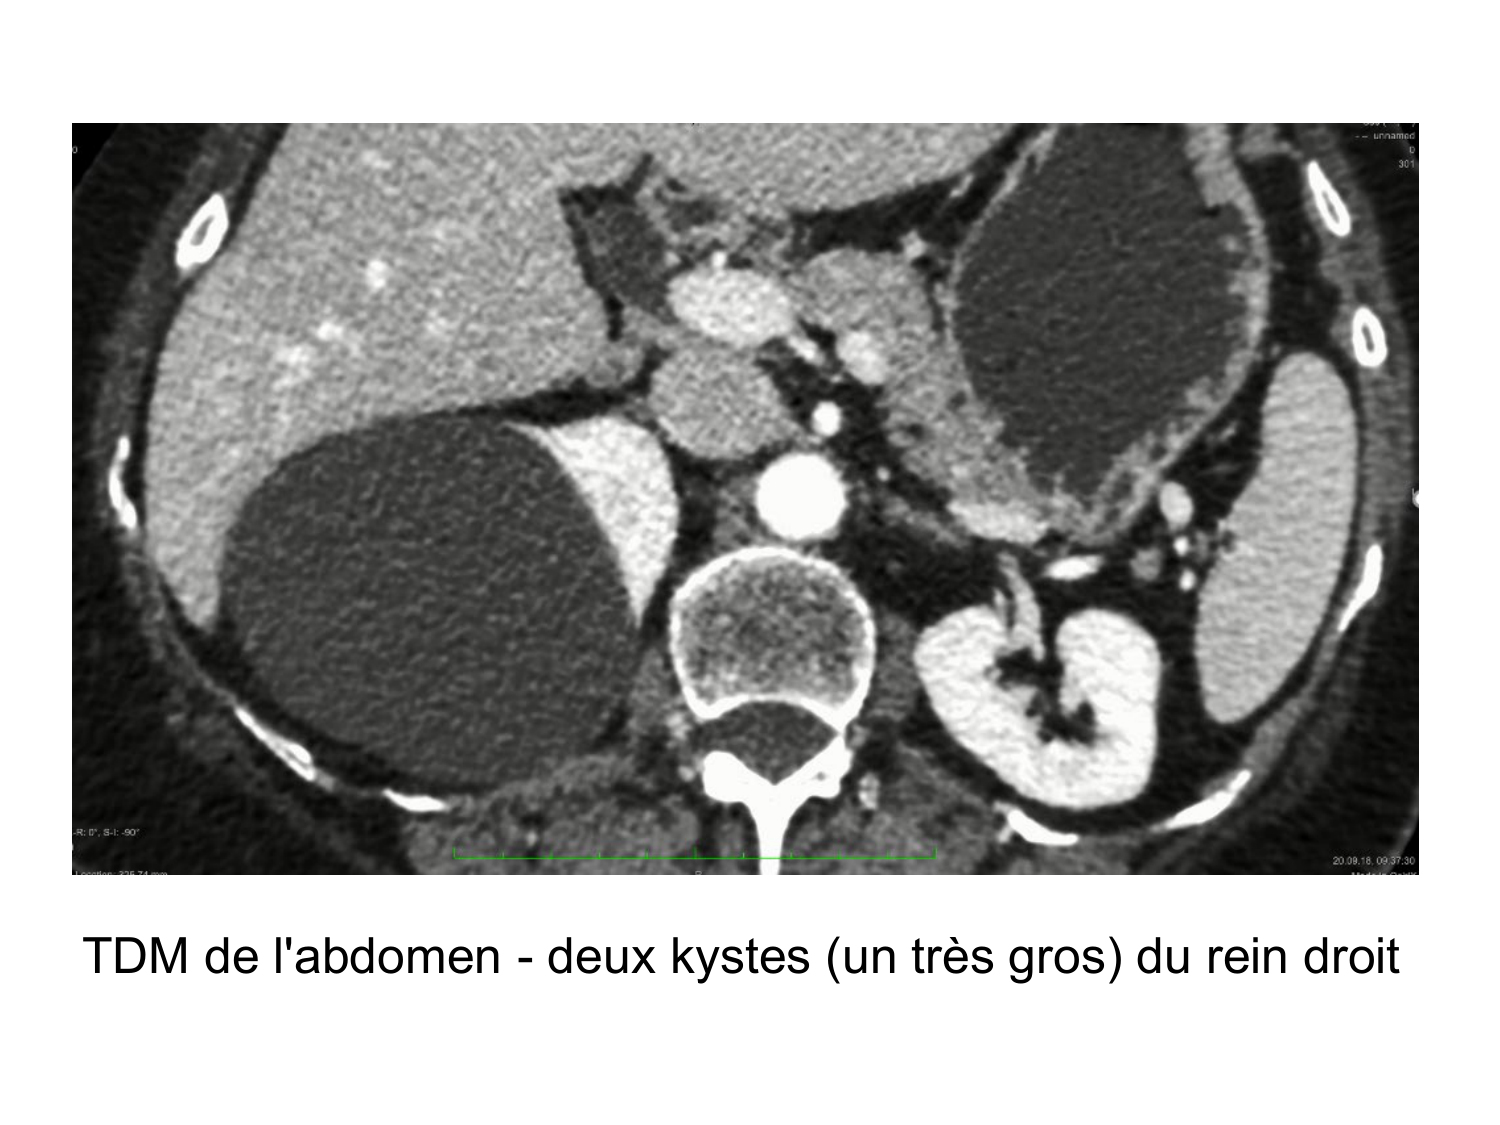

11.47 · Rein, voies urinaires et retropéritoine

Rein, voies urinaires et retropéritoine